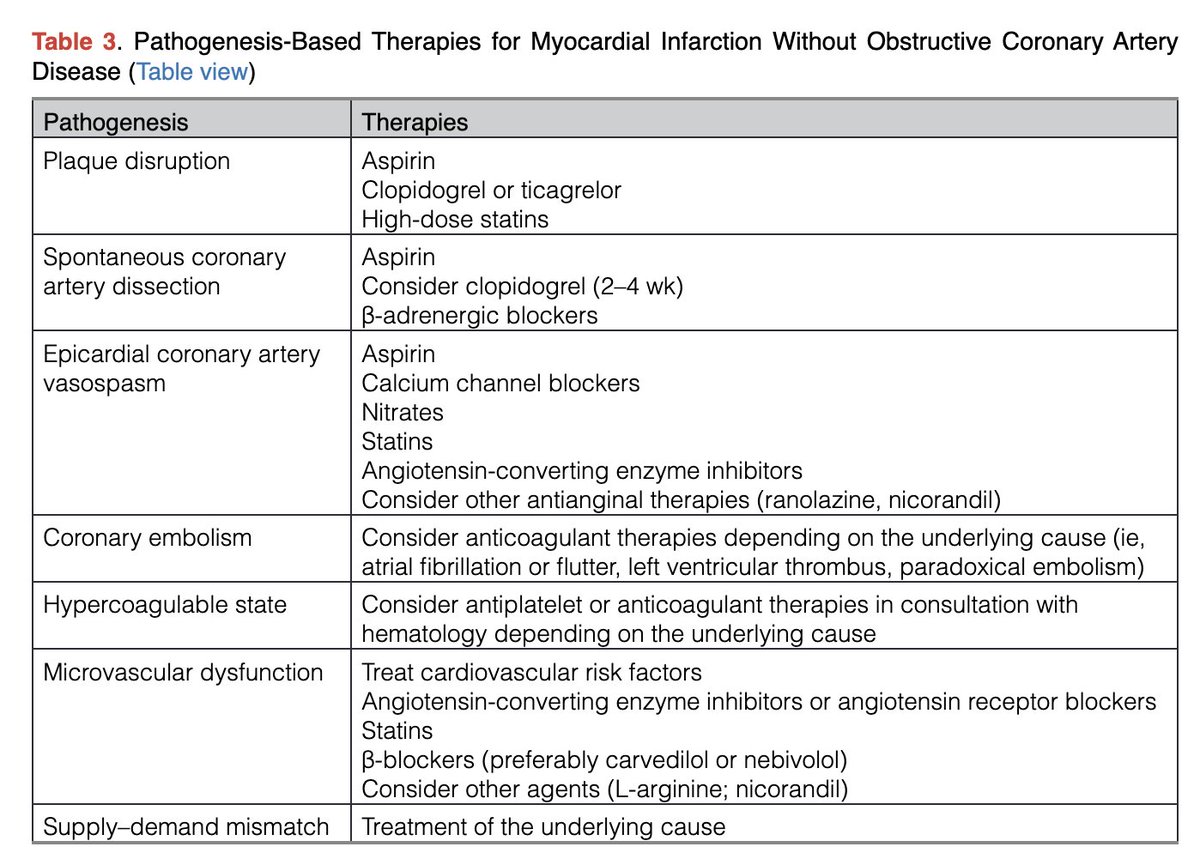

🔴State of the Art: Evaluation & Medical Management of Nonobstructive Coronary Artery Disease in Patients With Chest Pain: A Scientific Statement @CircAHA #Cardiology #CardioEd #FOAMed #AHA2025